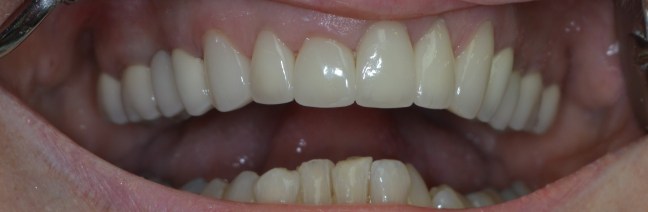

Kozmetikai és funkcionális kezelés: a kopott, elszuvasodott fogak szanálásával, hiányzó frontfogak híddal történő pótlásával, harapás megemelésével.

A választott korona típusa: CAD/CAM (komputer vezérelt tervezés/megmunkálás) technológiával készült cirkónium (fémmentes) szóló koronák, front híd.

A választott fogszín: BL 3 .

A protetikai munka elkészülésének ideje: 10 munkanap.